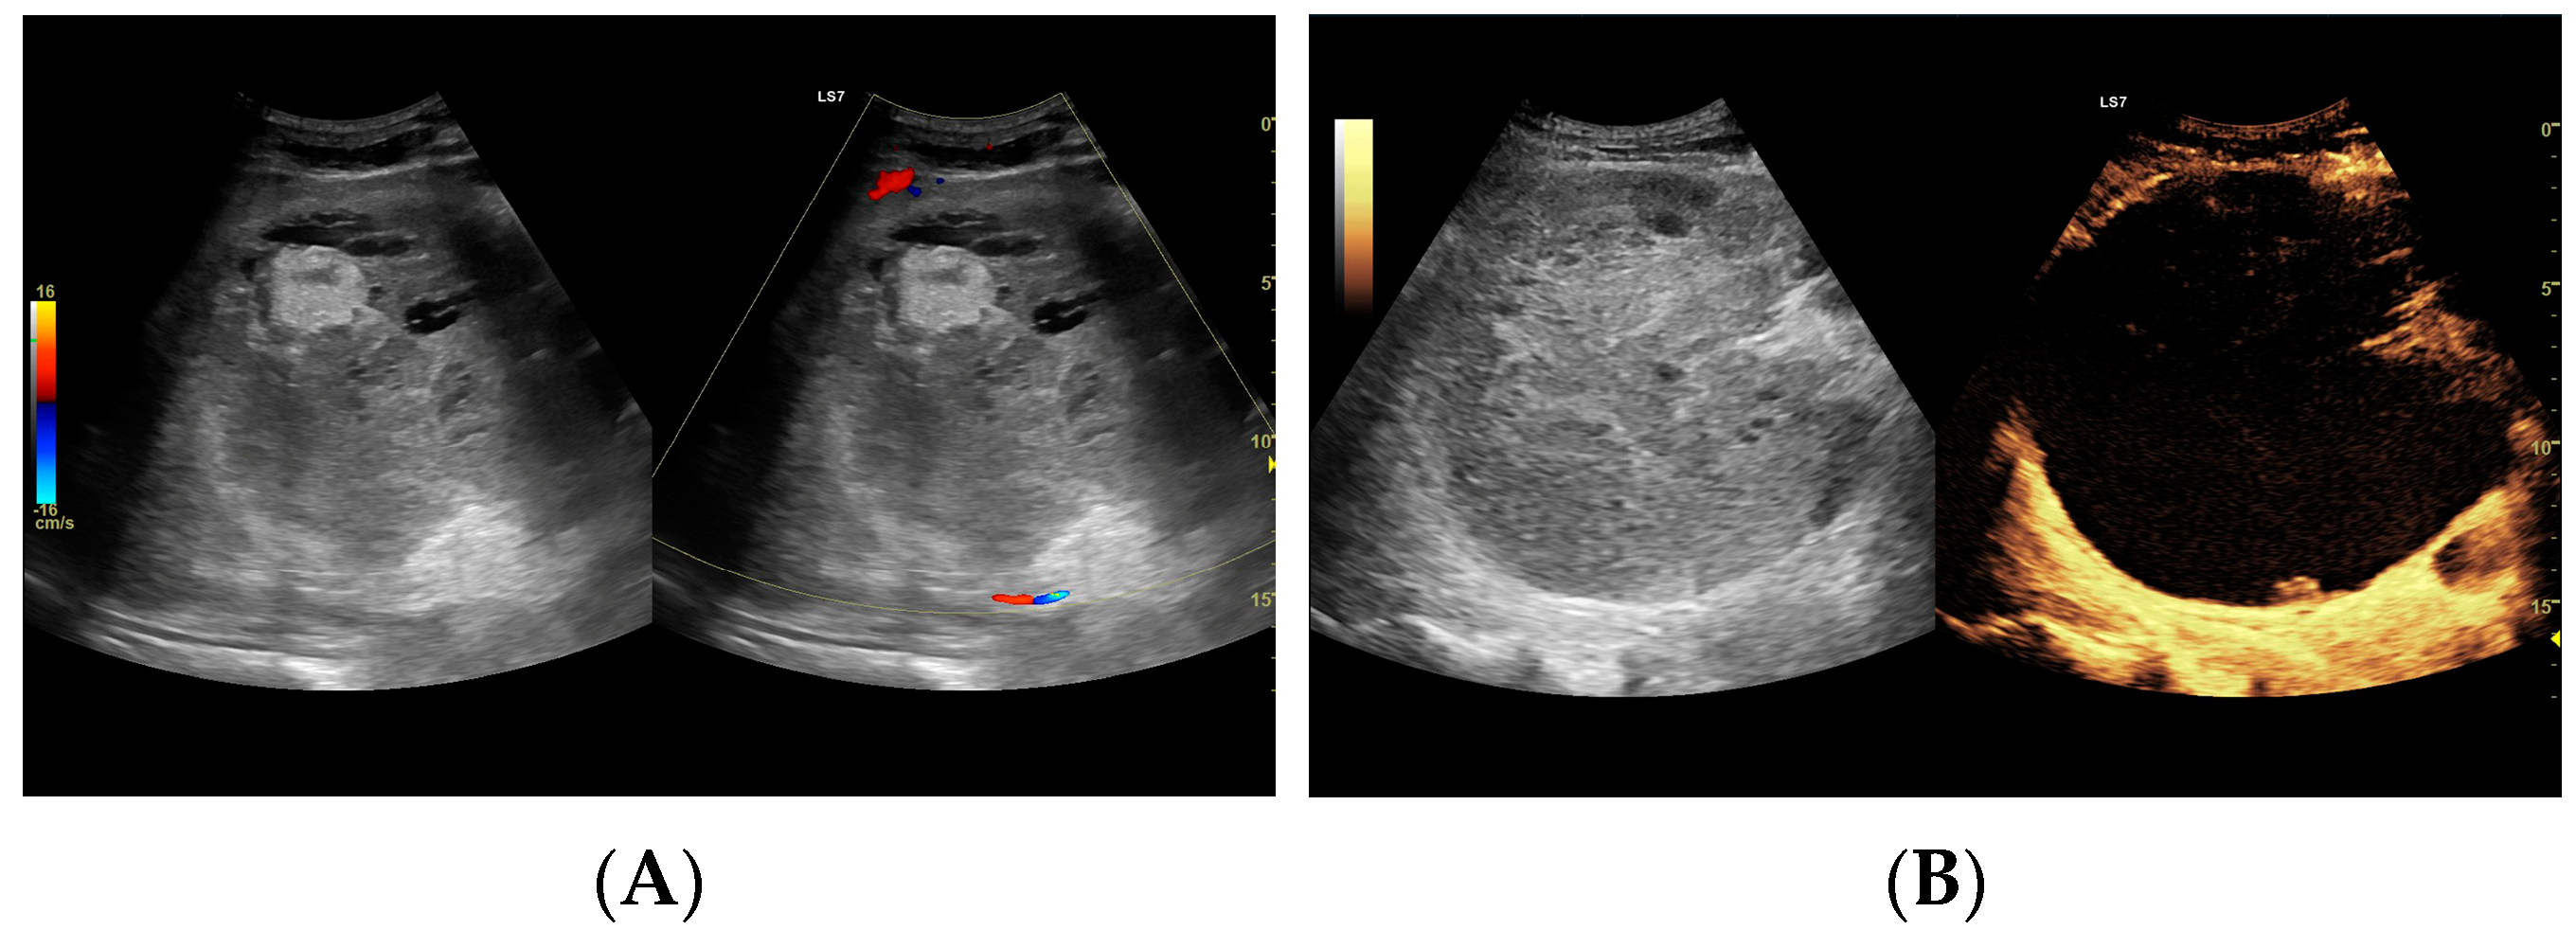

Figure 8.

Focal liver lesion diagnosed as a type III abscess. (A) Post-contrast image on CT. (B) B-mode ultrasound: the fluid component of the lesion is difficult to define. (C) CEUS: the fluid component of the lesion is visible, and the patient is qualified for percutaneous drainage. (D) Post-contrast image on CT: Follow-up examination one week after placement of drains shows a visible reduction in the fluid component. The lesion is transitioning from type III to type II, with a visible “honeycomb” sign. (E) B-mode ultrasound: the fluid component of the lesion remains challenging to define. (F) CEUS: the fluid component of the lesion is visible, indicating regression from stage III to II. (G) Post-contrast image on CT: follow-up examination performed 1.5 months after placement of percutaneous drainage reveals a visible residual lesion. (H) B-mode ultrasound: a residual lesion is visible. (I) CEUS: the residual lesion shows the fluid component to be completely invisible, with a connective tissue scar present.